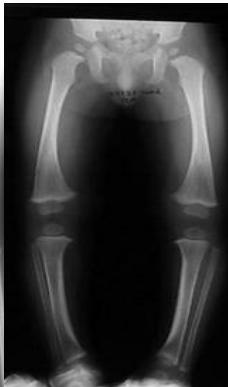

Radiological Assessment

Indications: X-ray when severe or possibly pathologic

Recommended Views:

- Standing AP film: Long film (hips to ankles) with patellae directed forwards

Radiological Parameters to Assess:

- Medial Physeal Slope

- Femoral-Tibial Axis